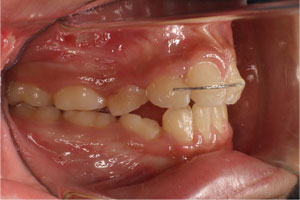

こちらの初診(男性)の患者さんは、開咬合 / 叢生歯列の症状がありました。

1期治療 8歳9ヶ月 2期治療 12歳4ヶ月から治療を開始し、1期治療 7ヶ月 2期治療 2年5ヶ月の間、スタンダードエッジワイズ法(与五沢エッジワイズシステム)を用い矯正治療を行いました。

| 症例分類 | 開咬合 / 叢生歯列 / 偏位咬合 | |||||||||||||||||||||||||||||||||||||||||||||||||||||||||||

| 動的治療期間 | 1期治療 7ヶ月 2期治療 2年5ヶ月 | |||||||||||||||||||||||||||||||||||||||||||||||||||||||||||